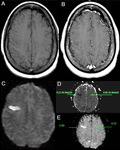

Acidente vascular cerebral (AVC) isquêmico

Tomografia computadorizada (TC) de crânio sem contraste mostrando infarto ganglionar basal isolado esquerdo subagudo com efeito de massa protuberante frontal esquerda

Cortesia do BMJ Case Reports 2009; (doi:10.1136/bcr.10.2008.1139)